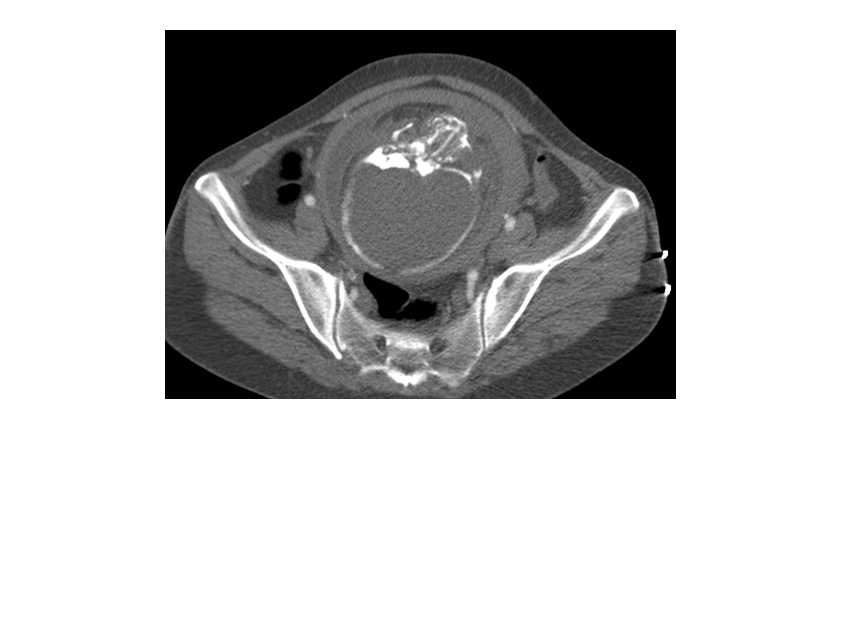

CT表现:自主动脉根部起至腹主动脉肾动脉水平可见撕裂之动脉内膜瓣影,子宫腔内可见胎儿影。

诊断结果:妊娠合并主动脉夹层(I型)。

显示冠状动脉、头臂动脉、腹腔内脏器动脉及髂动脉起源于真或假腔、是否受压推移。如果受夹层累及,可见内膜片线状充盈缺损影自血管开口处伸入分支血管腔内。